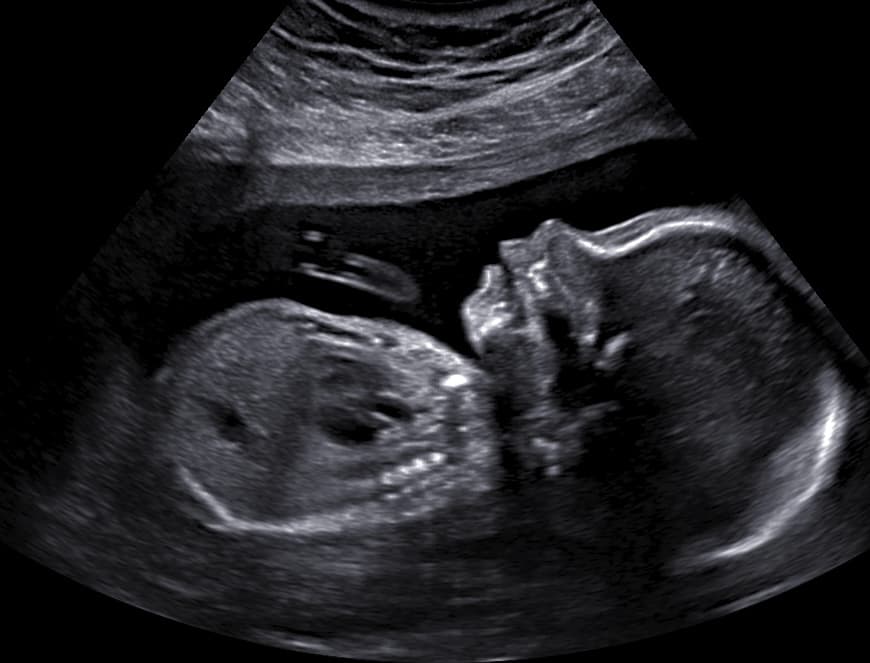

Explore our collection of ultrasound images and clinic photos. See the quality and clarity of our technology and the comfort of our facilities.

Book an appointment today and capture beautiful images of your baby. Our state-of-the-art technology provides clear, detailed ultrasound images for you to cherish forever.